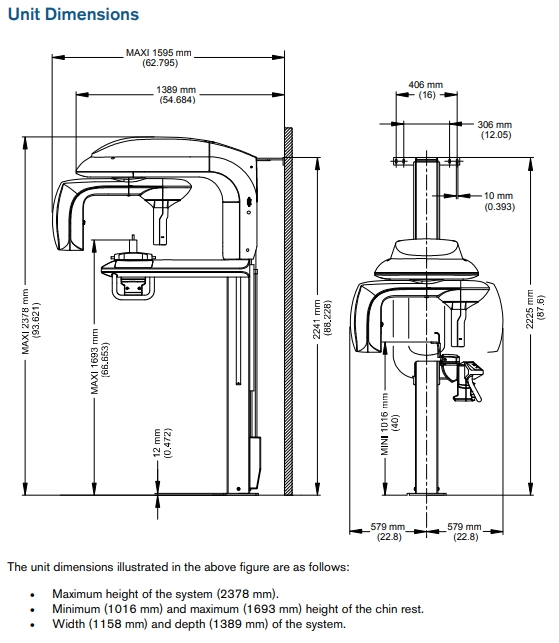

Wheelchair Accesible - The CS 9300 system's open design and motorized height adjustment accommodates patients of any size, including those in wheelchairs.

Standing Design - Face-to-face positioning puts patients at ease, facilitating positioning and minimizing risk of movement.